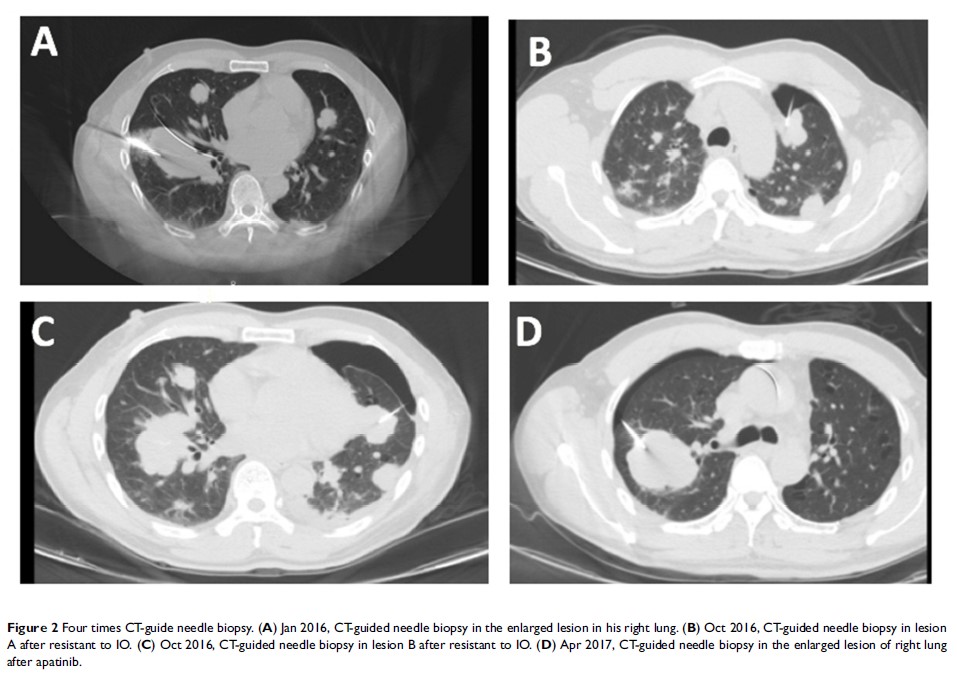

Case Report

因 SCLC 转换而导致的第三代 TKI 耐药:一例病例报告和简要评述